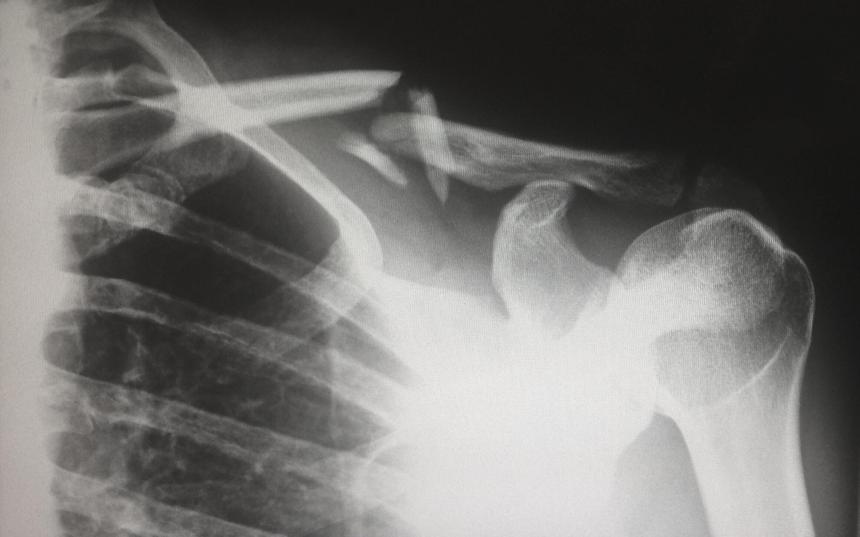

Учёные из Университета Отаго обнаружили, что множественные переломы в детстве повышают риск остеопороза и переломов в зрелом возрасте.

Авторы новой научной работы изучили историю переломов у группы людей среднего возраста. Оказалось, что есть зависимость от переломов в детстве — у людей, переживших это, был в два раза выше риск сломать кость во взрослом возрасте.

У женщин также наблюдалось снижение плотности костной ткани бедра. Отмечается, что повышенный риск переломов не был связан с поведенческими факторами.